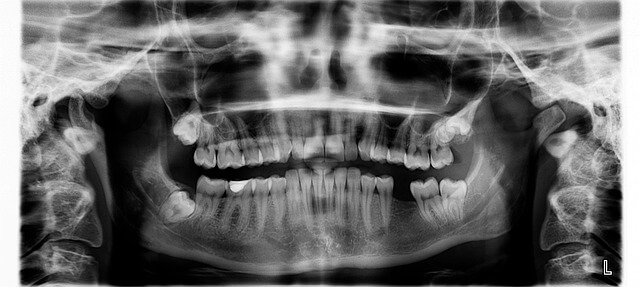

- *치아교정 받을 때 보험적용이 되는 경우는 주로 선천적인 악안면 기형, 저작 기능 장애, 심한 부정교합 같은 상태예요. *치아교정 진행하는 치과에서 질병코드(Q35~Q37, K07.1 등 포함) 진단받으면 건강보험 및 실손보험 일부 적용 가능합니다. *이런 고민 하셨다면 치료 목적이 분명할 때 진단서, 치료 기록, 영수증 등 꼼꼼히 준비해서 보험사 심사에 제출하는 것이 핵심입니다. *치아교정 실제 경험자는 먼저 치과 상담 후 보험사와 사전 확인, 그 후에 청구해야 승인 확률이 높다더라구요.